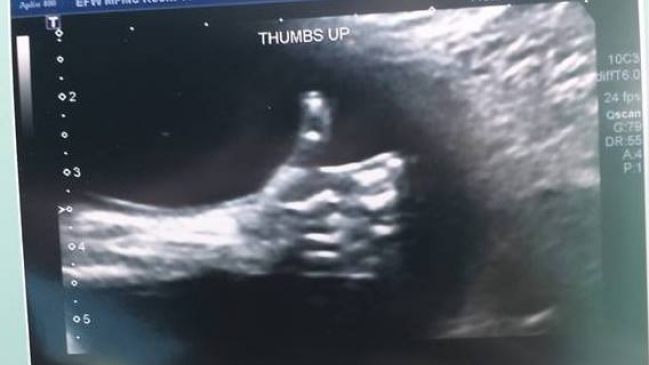

El asombroso "Me gusta" de un feto desde el útero de su madre que se hizo viral

Nicole Kim publicó una imagen donde se puede ver la mano del hijo que espera con el pulgar hacia arriba, así como en Facebook.

La imagen se convirtió en viral en las redes sociales.